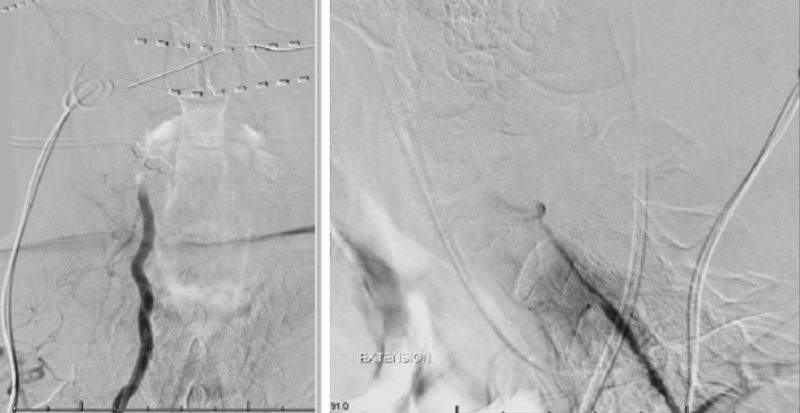

On rotation to the left, the patient experienced mild symptoms, however no significant Vertebral Artery or basilar reduction in flow was observed. On rotation to the right, the patient experiences slightly more moderate symptoms, however no significant Vertebral Artery or vascular reduction flow was observed. On hyper extension of approximately 10-15 degrees, passively performed by the patient until symptoms are reproduced, angiogram demonstrates complete occlusion of the right Vertebral Artery at approximately the C2-C1 level. (Figure 5)

It is unclear whether there is a specific bony osteophyte or soft tissue mass that is resulting in the compression. Live fluoroscopy within the neutral and extension position does demonstrate extensive arthritis and hypertrophic changes within the C1/C2 region, however specific anatomic compression is difficult to determine.

Dynamic provocative fluoroscopy failed to reveal significant Vertebral osseous instability (Figure 2A), however, Transcranial Doppler Flow velocities in the distal right Vertebral and Basilar Artery are markedly reduced during Extension of the Neck (Figure 2B).